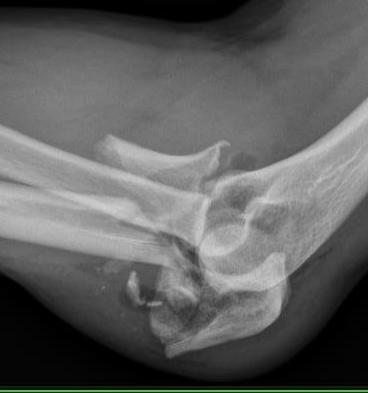

Monteggia variant

Elbow dislocation + olecranon fracture + radial head/neck fracture +/- coronoid fracture

Identify olecranon fracture

- isolate and protect ulna nerve

- dissection out medial and lateral proximal ulna

- reduce and plate olecranon